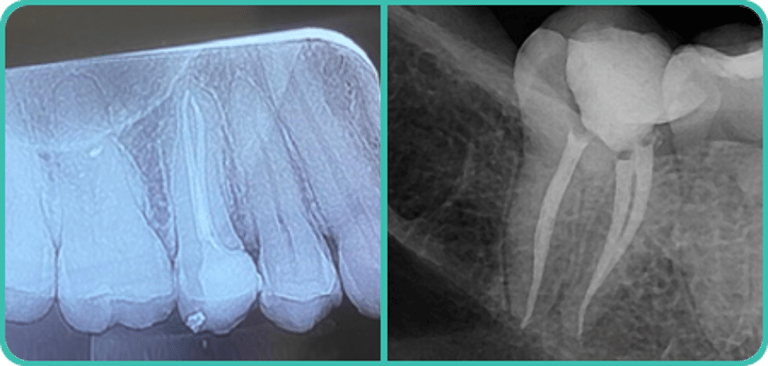

Procedimentos básicos:

Limpeza dental, remoção de tártaro, fluorterapia, pequenas restaurações, clareamento, tratamento de doenças gengivais, extrações, tratamento de traumas dentários e tratamento endodôntico (canal radicular).